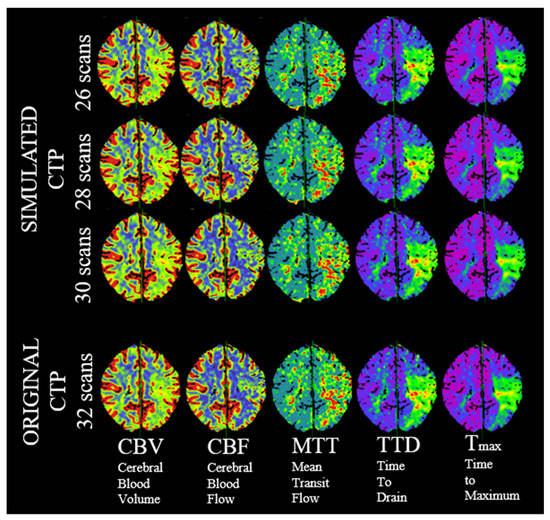

2.4. Study Design